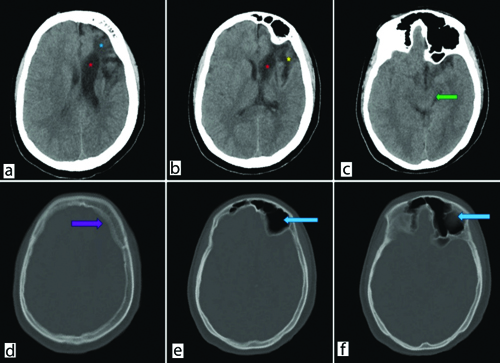

On Computed Tomography (CT) scan [Table/Fig-2a-f], gliotic and encephalomalacia changes were observed in the left frontoparietal region with dilatation of the left lateral ventricle. Left-sided cerebral hemiatrophy, left-sided midbrain atrophy likely due to Wallerian degeneration and cerebellar atrophy were noted. Hyperpneumatisation of the left frontal sinus and bilateral mastoid air cells, along with diffuse calvarial thickening, were also observed. After carefully ruling out various neurological diseases that can present with similar symptoms, especially Sturge-Weber syndrome and Rasmussen encephalitis, our patient was diagnosed with DDMS.

a and b) Non contrast Computed Tomography (NCCT) Brain axial images demonstrate left sided gliotic changes involving frontal lobe (blue asterisk) with ex-vacuo dilatation of left lateral ventricle (red asterisks). Prominent left sylvian fissure (yellow asterisk); c) Left-sided midbrain atrophy (green arrow); d) Bone window image shows bony calvaria thickening (violet arrow) along left side of frontal bone; e and f) Hyper pneumatisation of left frontal sinus (blue arrows).